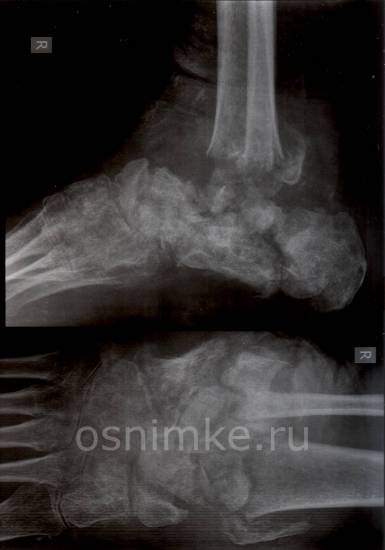

Здравствуйте. На рентгенограммах костей правого голеностопного сустава и костей предплюсны правой стопы в боковой и прямой проекциях определяется полная потеря структурности и уменьшение размеров костей предплюсны, множественные просветления и слабо выраженные включения остеосклероза.

Также в процесс вовлечены основания 2-5 плюсневых костей – множественные кистовидные просветления. Суставные щели практически не прослеживаются.

На фоне вышеописанных изменений – поперечные переломы дистальных мета-диафизов большеберцовой и малоберцовых костей, смещение костных отломков сзади и по ширине снаружи, контуры отломков нечеткие, неровные. Мягкие ткани в зоне интереса повышенной интенсивности.

Заключение: Посттравматический хронический остеомиелит на фоне переломов костей нижней трети правой голени. Дифференцировать с патологическими переломами на фоне туберкулёза костей правой голени (артритическая фаза).